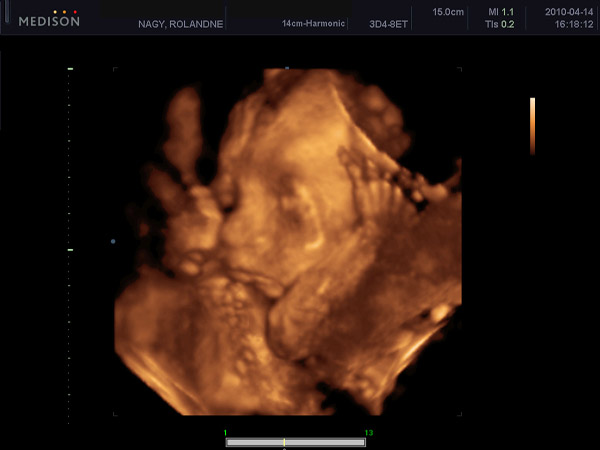

Egész nap a városban voltunk :) Rossz volt az időnk, de a kedvem picit jobb lett, h megpillanthattam a szívem alatt dobogó kis puncus fél arcát... Sajnos a kezét szinte mindig feltartotta, így nem sokat látthattam belőle, de legalább tudok nektek képet küldeni. :) Igaz nemsok minden vehető ki, de folyton mozgott és befelé fordult :(

Kép Dominika a 24.héten